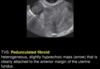

Pedunculated Fibroid on TVS

A